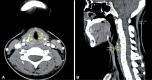

Respiratory involvement in Crohn disease (CD) is rare condition with only about a dozen reported cases. We report the first case of CD with tracheal involvement in Korea. An 18-year-old woman with CD was hospitalized because of coughing, dyspnea, and fever sustained for 3 weeks. Because she had stridor in her neck, we performed computed tomography of the neck, which showed circumferential wall thickening of the larynx and hypopharynx. Bronchoscopy revealed mucosal irregularity, ulceration, and exudates debris in the proximal trachea, and bronchial biopsy revealed chronic inflammation with granulation tissue. Based on these findings, we suspected CD with tracheal involvement and began administering intravenous methylprednisolone at 1 mg/kg per day, after which her symptoms and bronchoscopic findings improved.